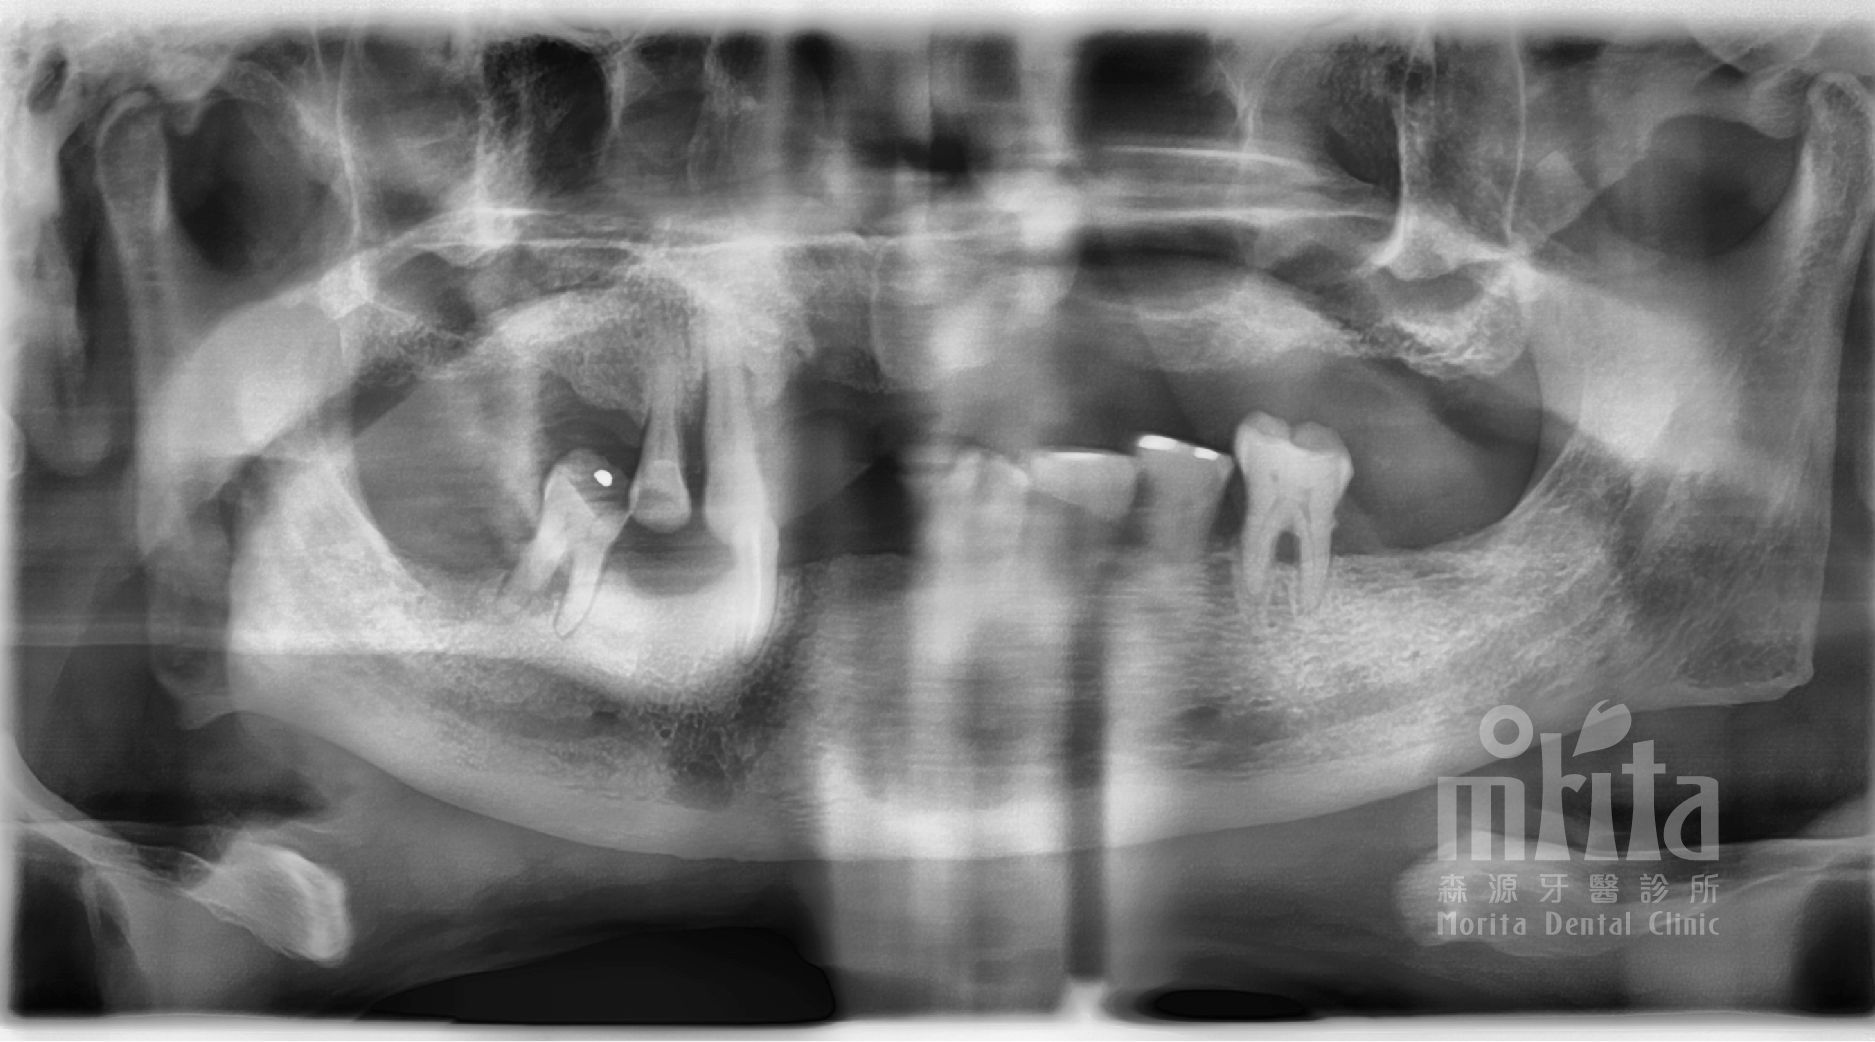

經過完整的事前評估與治療計劃說明,賴伯伯對於森源的醫療團隊感到十分有信心,於是開始進行一日假牙治療。